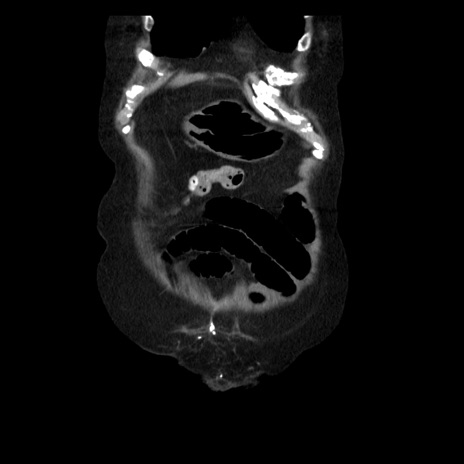

症例14(冠状断像)

【症例】 90歳代女性

【主訴】 腹痛・嘔吐

【現病歴】今朝から左側腹部痛を認めた。 経過観察していたが、嘔吐を認めたため来院。

【既往歴】 子宮癌術後

【身体所見】 意識清明、BP 127/54mmHg、P 98bpm Sp02 95%(RA)、BT 35.8°C、腹部平坦・軟腸ぜん動音聴取良好、右下腹部圧痛(+) 反跳痛なし

【データ】WBC 9800、CRP 0.46